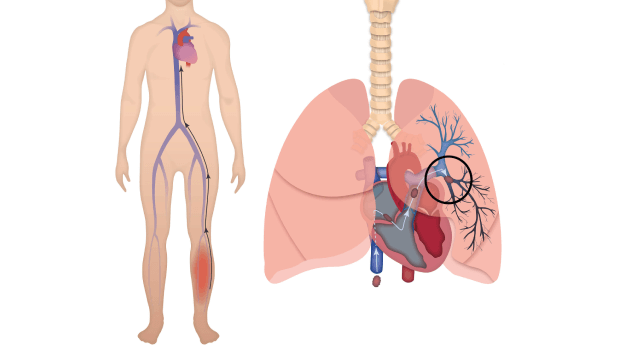

آمبولی یا لخته شدن خون در ریهها و سیستم گردش خون یکی از عوارض جدی پس از هر نوع جراحی است. بسیاری از بیماران نگران هستند که خطر آمبولی تا چه مدت پس از عمل وجود دارد و چگونه میتوان آن را شناسایی و پیشگیری کرد.

آمبولی زمانی رخ میدهد که لخته خون (ترومبوس) در رگها تشکیل شود و سپس به ریهها منتقل شود. این وضعیت میتواند تهدید کننده زندگی باشد و نیازمند تشخیص و درمان فوری است.

- بی حرکتی بعد از جراحی: کم شدن تحرک باعث تجمع خون و تشکیل لخته میشود.

- نوع جراحی: عملهای بزرگ، به خصوص جراحیهای شکم، لگن و ارتوپدی، خطر آمبولی را افزایش میدهند.